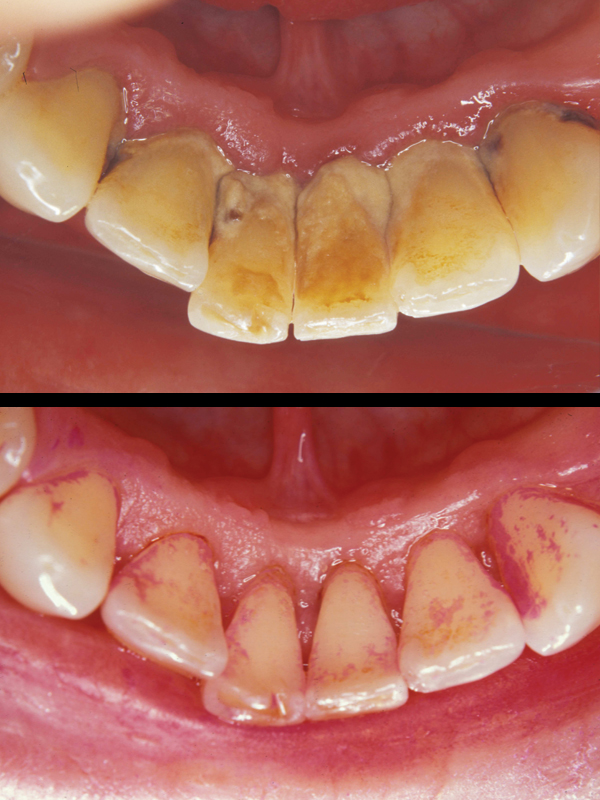

Gummy Smile

A “Gummy Smile” is a condition in which there appears to be too much gum showing when smiling and teeth that look “too short”. This is known as Altered Passive Eruption. A gummy smile is quite unsightly and can be embarrassing because it looks like you have “baby teeth”.

In most cases the condition can be easily treated in one visit by “sculpturing and reshaping” the soft tissue around the involved teeth, revealing more of your natural tooth that has been “hiding” underneath.

As one can see in the following cases, treatment can yield a dazzling result, leaving our patients with “something to smile about”!